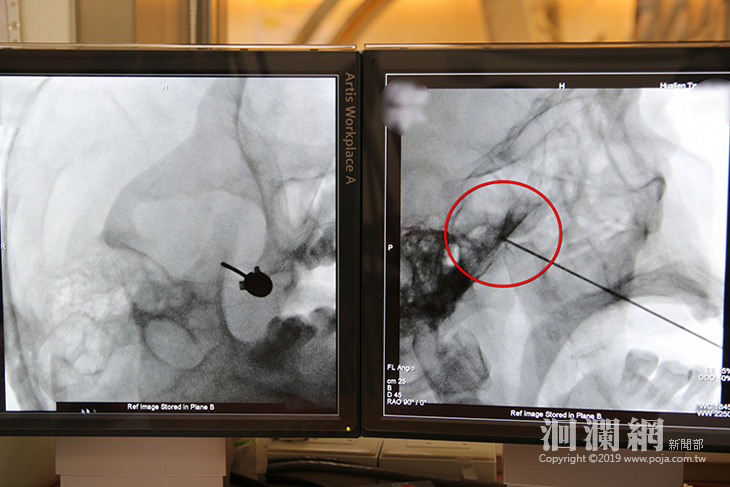

初期先以高頻熱凝療法治療林先生右臉的三叉神經周邊,但效果只能持續約三個月,去年十一月開始深入到三叉神經的神經節灼燒。王柏凱主任表示,高能量透過電擊針尖端引發電磁場產生熱能,設定溫度後調節神經痛,止痛的效果能持續半年,治療的藥物也能減少許多,讓病人生活品質提升,半年後若是疼痛感加劇,病人可以再次進行高頻熱凝療法治療。

麻醉部疼痛科主任王柏凱使用高頻熱凝療法將電擊針深入至三叉神經的神經節治療。